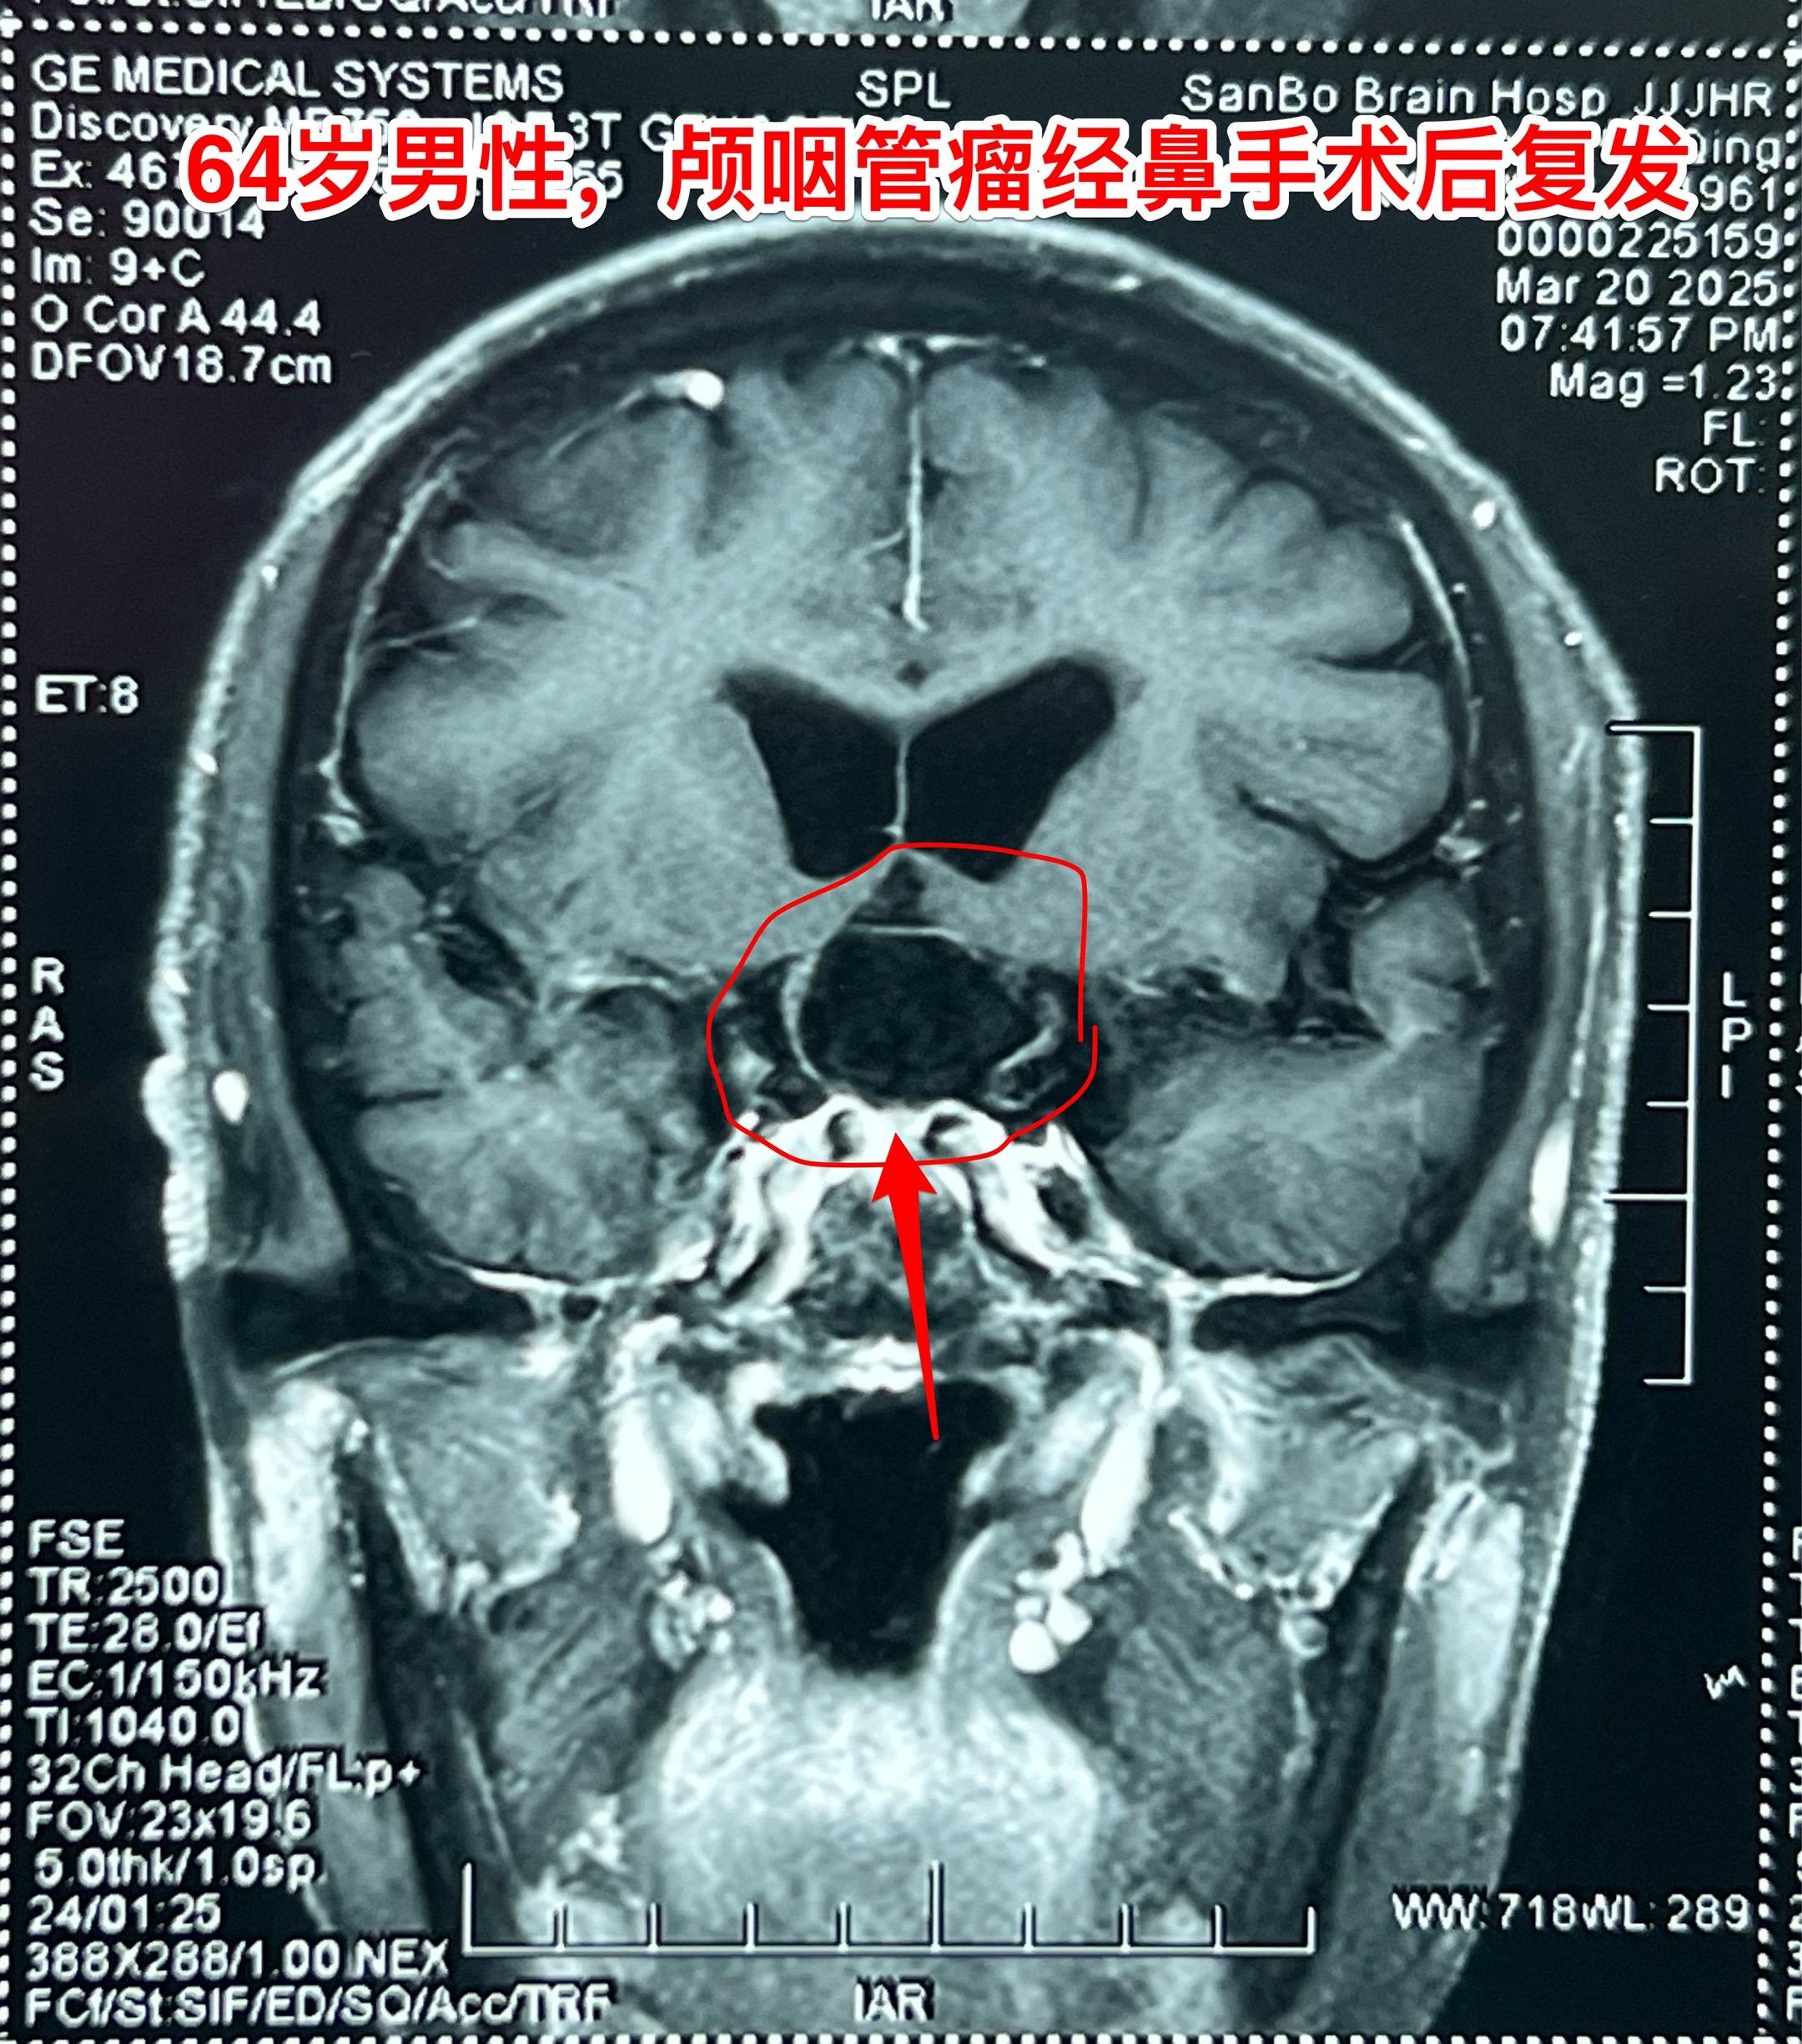

3月28日两个颅咽管瘤手术 两个都是经鼻手术手术后复发的颅咽管瘤手术。我采用了开颅手术。 第一个是64岁山西人,颅咽管瘤手术后再次出现视力下降,复查磁共振显示肿瘤复发。肿瘤是囊性乳头型颅咽管瘤,没有钙化。 第二个是32岁的湖南小伙。肿瘤有钙化。 今年春节后我科颅咽管瘤中经鼻手术后复发的病人比例明显升高了。与近十年经鼻内镜手术广泛开展是有关系。 无论是哪种手术方案,只有效果好、复发率低,病人才会满意。